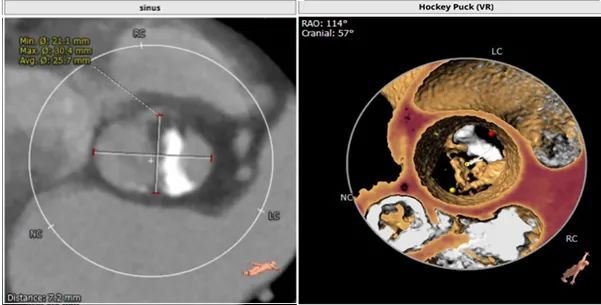

主动脉根部解剖CT影像

TYPE 0型主动脉瓣,瓣环径22mm,瓣上结构分析仅有左侧窦单瓣叶钙化,右侧窦瓣叶柔软无支撑。应用downsize策略(23mm瓣膜)不排除会出现瓣膜固定不稳,飞瓣或下滑可能。

左侧窦瓣叶钙化,左侧窦平且冠脉高度不足,右侧窦也不大,且预计瓣叶长度高于右冠高度,双侧冠脉均有遮挡风险。